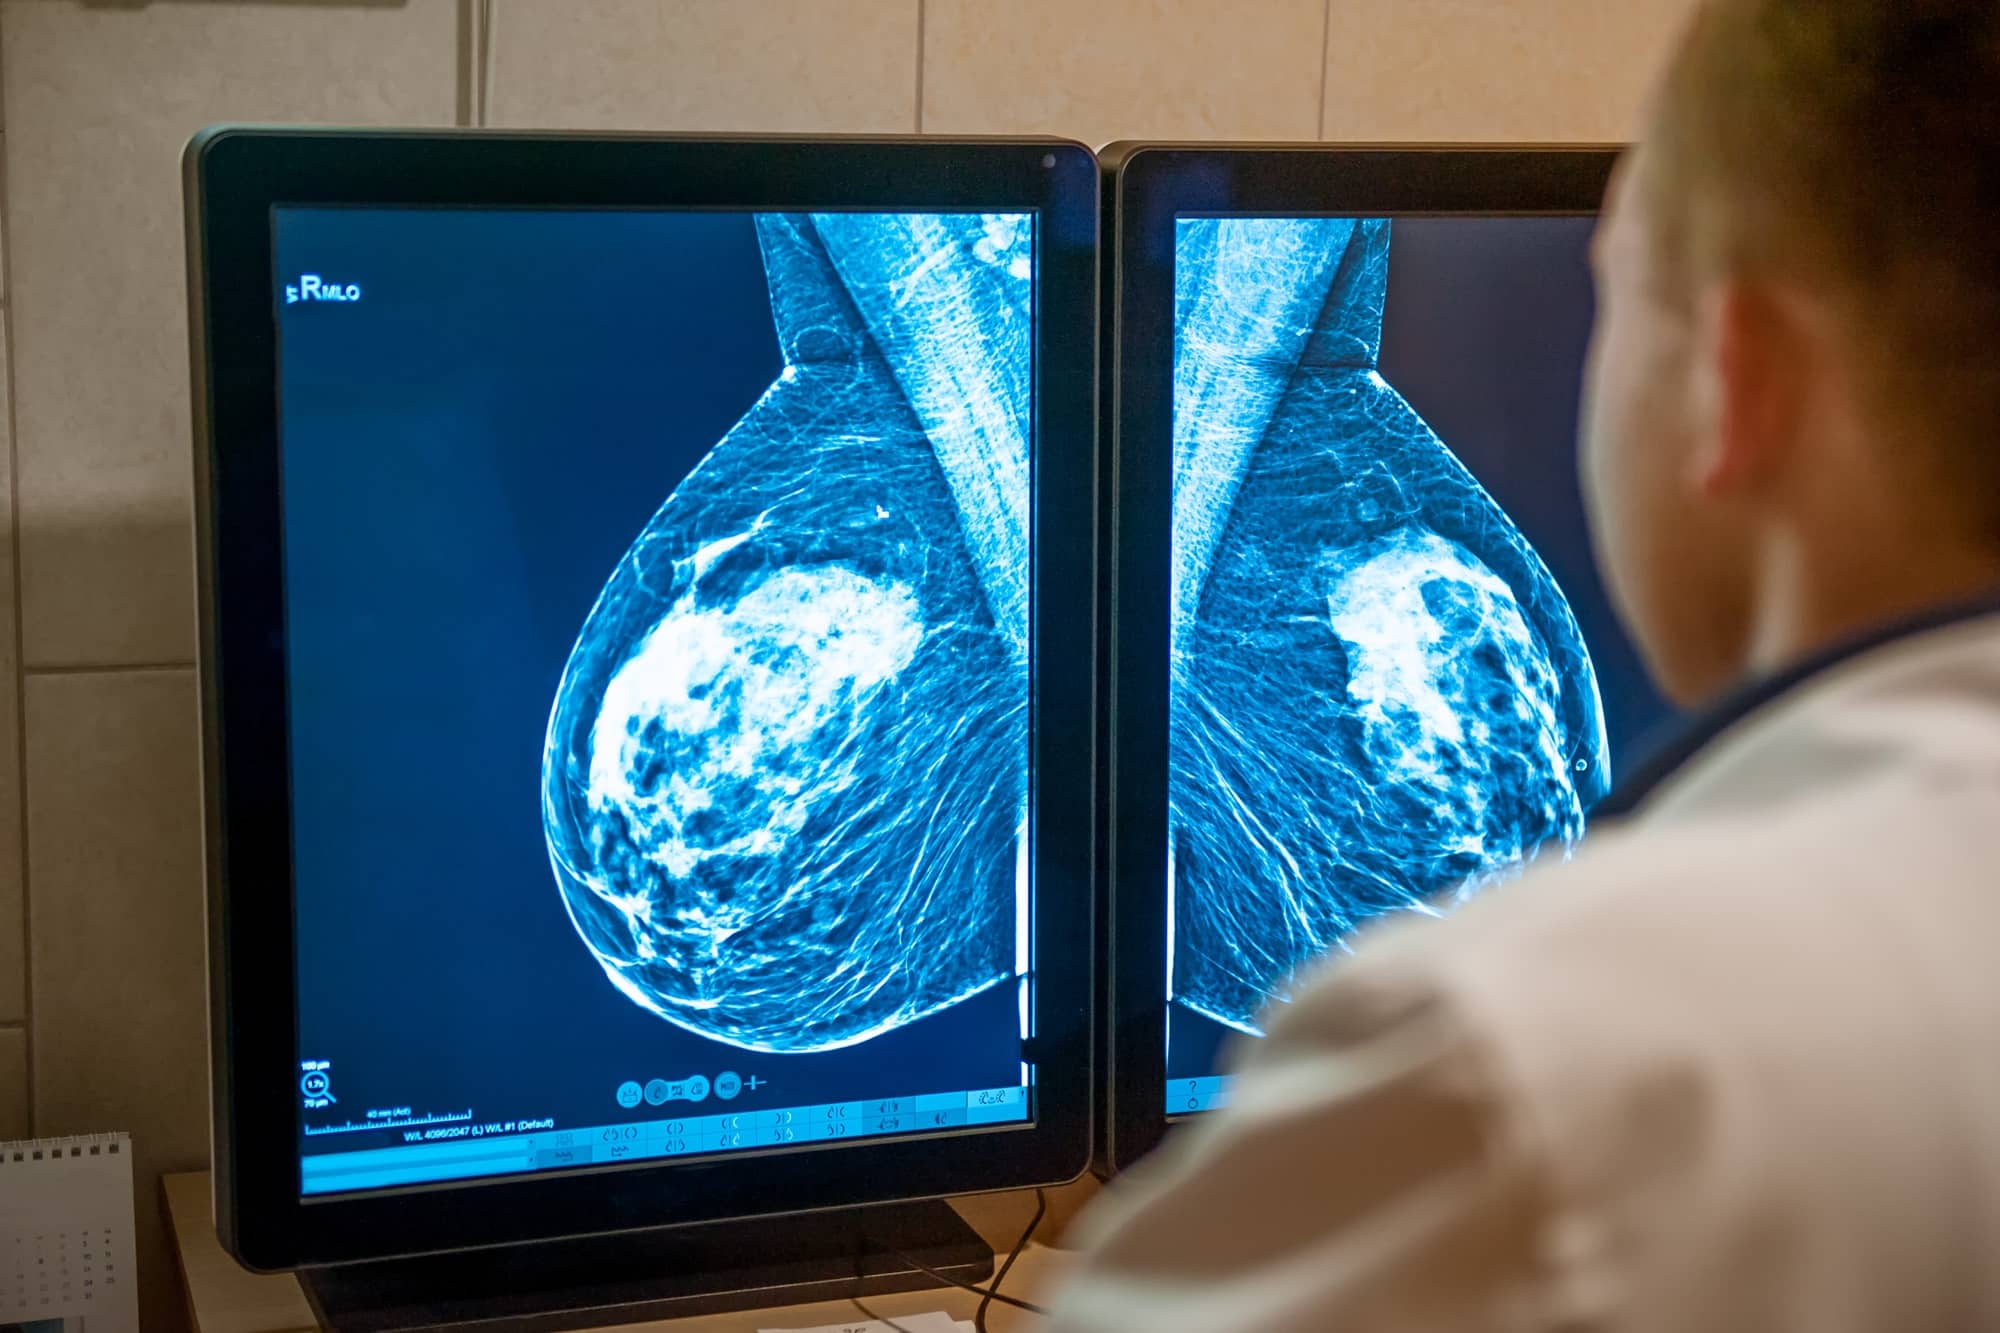

Postęp w leczeniu raka piersi jest ogromny i przekłada się na realne leczenie. W Polsce brakuje jednak specjalistów onkologii klinicznej i łatwego dostępu do najnowocześniejszych terapii.

Za jeden z największych przełomów ostatnich lat w leczeniu raka piersi uznałabym indywidualizację terapii onkologicznych. Ogromnym postępem jest też odejście od rutynowych amputacji piersi – obecnie w wiodących ośrodkach zdecydowana większość chorych leczona jest z zachowaniem piersi lub – jeśli amputacja była konieczna – z rekonstrukcją piersi. Zmniejsza się też ingerencja chirurgiczna w zakresie węzłów chłonnych – kiedyś rutynowo usuwano wszystkie, co przekładało się na wysokie ryzyko obrzęku chłonnego, który jest powikłaniem de facto na całe życie i bardzo uciążliwym. Zmienia się także radioterapia, stając się metodą coraz bardziej precyzyjną – wskutek tego minimalizujemy ryzyko uszkodzenia zdrowych narządów podczas leczenia. Powoli również ograniczają się wskazania do radioterapii, ponieważ leczenie systemowe staje się bardziej skuteczne, co przekłada się na mniejsze ryzyko nawrotu. A jeśli ryzyko to jest bardzo niskie, z pewnych metod możemy obecnie rezygnować. Ogromnym postępem jest więc i to, że możemy robić mniej, a wyniki leczenia mogą być nadal bardzo dobre, zaś jakość życia jest zdecydowanie lepsza, gdyż mniej jest powikłań leczenia.

Postęp w leczeniu nowotworów piersi najszybciej pojawił się w odniesieniu do raka piersi HER2+ – dzięki zastosowaniu leków celowanych nowotwór ten stał się jednym z najlepiej rokujących, choć wcześniej był jednym z rokujących najgorzej. Duży postęp jest też w nowotworach luminalnych, czyli hormonozależnych. W rakach potrójnie ujemnych również obserwujemy postęp leczenia, choć nie tak duży. Z kolei w raku powstającym w wyniku mutacji w genach BRCA są już leki, które wykorzystują mechanizm molekularny związany z brakiem białka kodowanego przez geny BRCA1, BRCA2. W Polsce dostęp do leków mamy obecnie nawet lepszy niż w innych, nieraz bogatszych krajach. Praktycznie wszystko, co może przekładać się na poprawę wyników leczenia, jest już u nas dostępne, m.in. dzięki październikowej aktualizacji listy leków refundowanych. Problemem jest to, że dostęp do kosztownych terapii możliwy jest w naszym kraju poprzez programy lekowe, co ogranicza takie leczenie jedynie do określonej liczby ośrodków – większych i bardziej „centralnych”; wiąże się też z dużą ilością biurokracji i pewnymi ograniczeniami formalnymi.